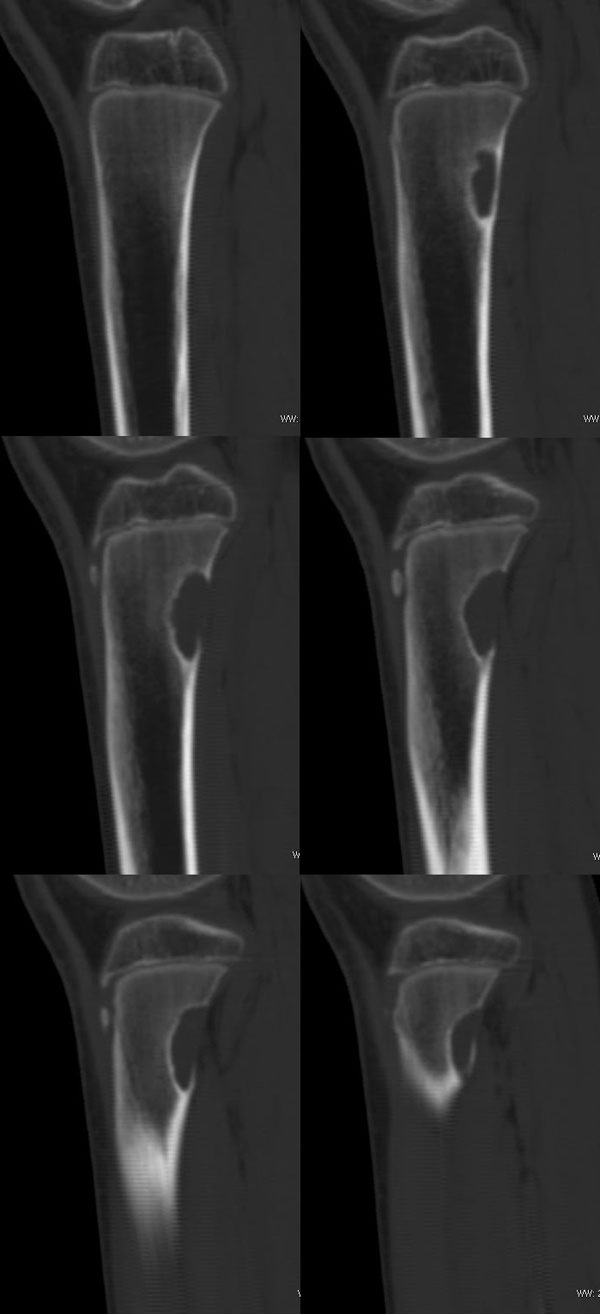

以下是引用37度在2010-1-7 12:22:00的发言:[br]左胫骨上段纤维性骨皮质缺损(非骨化性纤维瘤).

以下是引用dyqct在2010-1-7 14:54:00的发言:[br]考虑为左胫骨上段纤维性骨皮质缺损 ,可自愈.

以下是引用沉默是金在2010-1-8 18:51:00的发言:[br]非骨化性纤维瘤

以下是引用xkncyyhyq在2010-1-7 9:54:00的发言:[br]考虑为纤维性骨皮质缺损